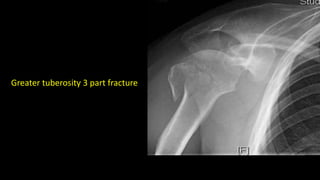

Greater tuberosity 3 part fracture

Greater tuberosity 3part fracture